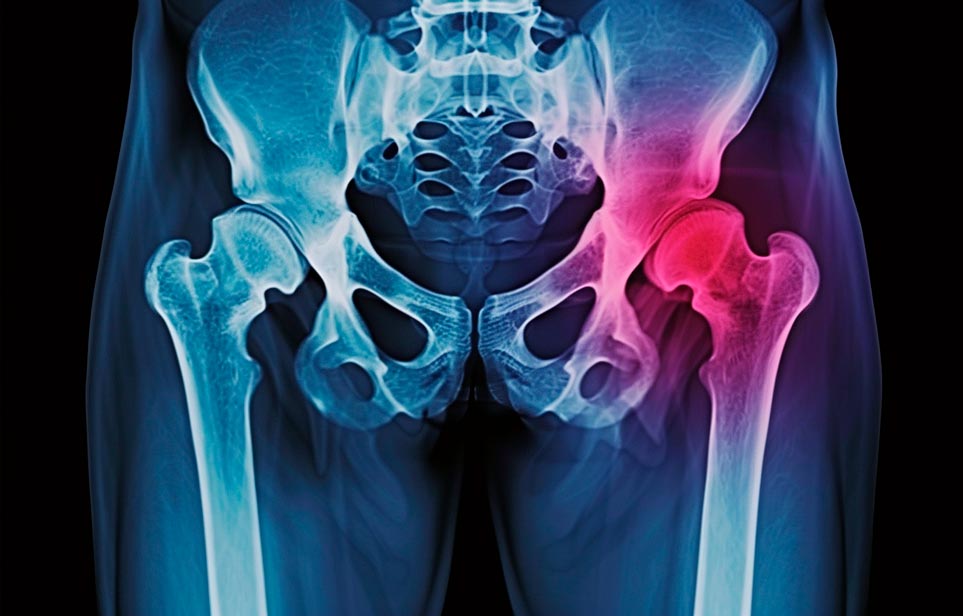

Реабилитация пожилых после перелома шейки бедра в Кстово

Эффективная и профессиональная реабилитация после перелома шейки бедра в Кстово осуществляется по демократичным ценам лучшими специалистами современной медицинской клиники «Заботливые люди» с применением персонального подхода к каждому пожилому человеку с такой тяжёлой травмой бедренной кости ноги. В процессе осуществления такой специализированной услуги все наши пациенты имеют возможность получения качественного и достойного обслуживания, эффективного восстановления. Лучший дом престарелых позаботиться о Вашем близком человеке.

Такая травма в большей части случаев возникает у граждан преклонного возраста. При её появлении на протяжении длительного времени сохраняются болевые и неприятные ощущения в области паха, при которых серьёзно ухудшается качество жизни, возникает множество последствий для его жизни и здоровья.

По какой симптоматике можно определить перелом шейки бедра?

Выявить его можно по возникновению следующей тревожной симптоматики:

- Визуально повреждённая нога сокращается на несколько сантиметром из-за сокращения мышц.

- Стопа выворачивается наружу.

- В лежачем положении человек не может поднять ногу.

При такой симптоматике важно незамедлительно обращаться к специалистам для получения всей необходимой помощи, терапии и восстановления после перелома шейки бедра. Если не оказать помощи старику, то это приведёт к гноению, инвалидности, иным видам осложнений.